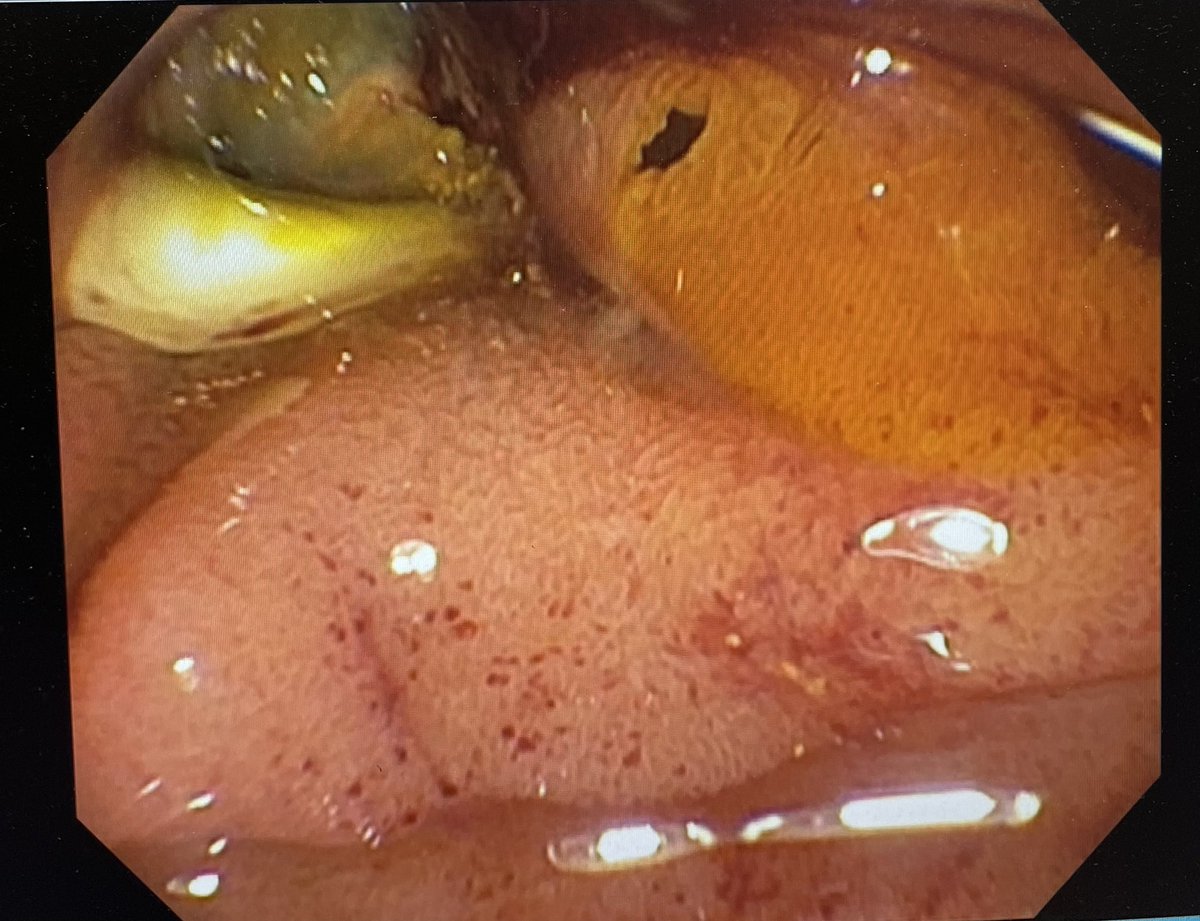

New @bostonsci Mantis clip closed this oozing fibrotic ulcer with one step, when other clips struggled.

Very nice!

#GITwitter